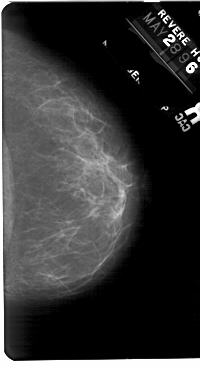

A_1833_1.LEFT_MLO

LEFT_MLO LINES 5491 PIXELS_PER_LINE 3076 BITS_PER_PIXEL 12 RESOLUTION 43.5 OVERLAY